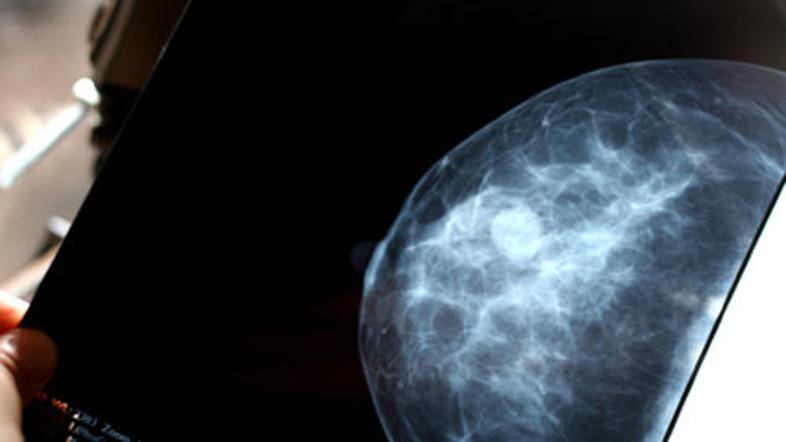

(Foto: iStockphoto) Žurnal24 main

V eni izmed britanskih bolnišnic so "pozabili" obvestiti ženske, pri katerih so odkrili raka na dojkah. Bolnišnica je že uvedla preiskavo zoper enega izmed radiologov.

Potem ko se je eni izmed pacientk zazdelo, da je nenavadno, da mamografija ni pokazala ničesar, čeprav je jasno otipala zatrdlino, so v bolnišnici Accrington Victoria Hospital še enkrat pregledali njene posnetke. Ti so jasno kazali, da ima ženska raka, ki je celo zelo napredoval.

Pregledali so vse radiološke posnetke za tri leta nazaj in ugotovili, da bi moral radiolog, ki jih je napravil, na dodatne preiskave poklicati kar 85 žensk, poroča Sky News.